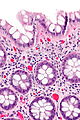

Normal colonic mucosa:

- Nuclei - round and basally located.

- Abundant goblet cells.

- Moderate inflammation.

- Paneth cells - present in right colon.

- Glands - straight, no branching; "test tube" shape.

- Test tube like glands.

- Minimal palisading.

- Nuclei <3:1 = height:width.

- No nuclear pseudostratification. †

- Deep part of crypt is more hyperchromatic than superficial component - important.

- The surface should be lighter staining than the deeper aspect, i.e. the deeper glands are dark blue and the superficial gland are light blue.